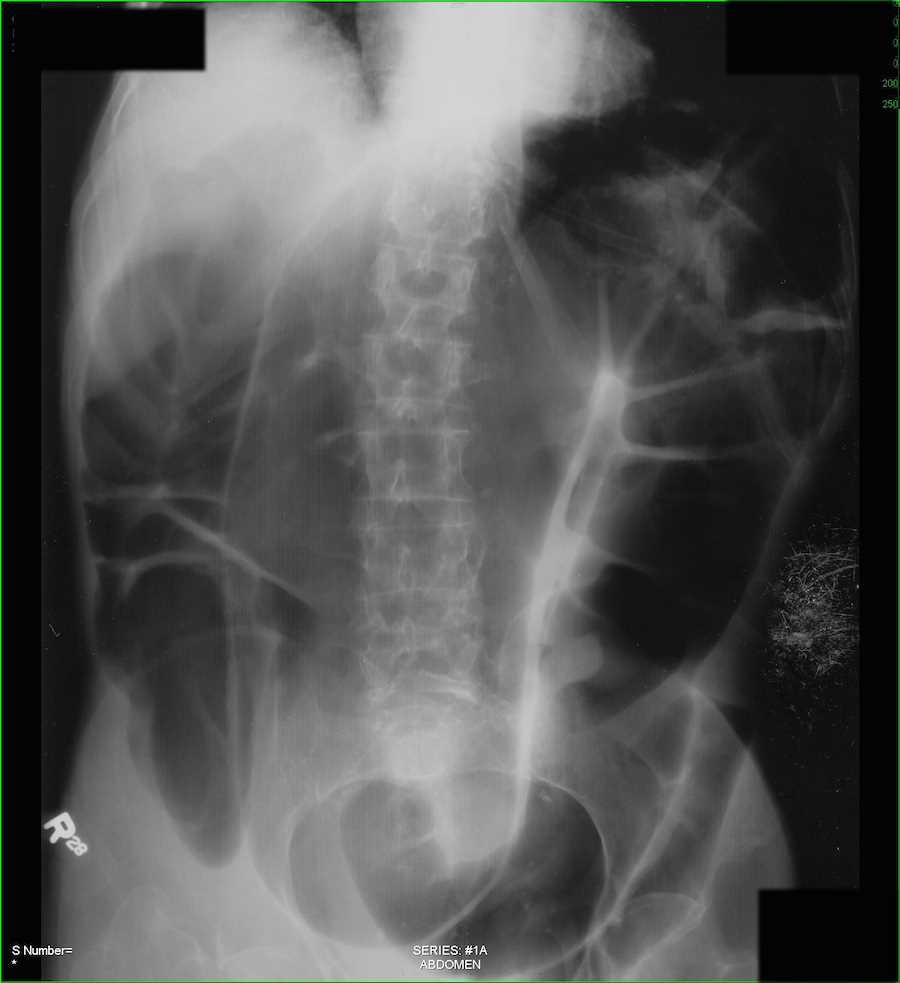

X ray abdomen showing ground glass appearance in entire abdomen caused Ground Glass Appearance X Ray Abdomen Also, a hepatic angle sign is seen when peritoneal fluid. Ground glass opacity (ggo) refers to the hazy gray areas that can show up in ct scans of the lungs. However, fluid levels may be absent. The finding can be one small spot all the way to. Postnatal usg demonstrated two cystic masses closely related to ileum. Ground glass looks. Ground Glass Appearance X Ray Abdomen.

X ray abdomen showing ground glass appearance in entire abdomen caused Ground Glass Appearance X Ray Abdomen These areas show increased density inside the lungs which could indicate. Ground glass opacity (ggo) refers to the hazy gray areas that can show up in ct scans of the lungs. However, fluid levels may be absent. A “soap bubble” or “ground. Ground glass looks hazy or cloudy compared to the normal dark lung. Also, a hepatic angle sign is. Ground Glass Appearance X Ray Abdomen.

X ray abdomen showing ground glass appearance in entire abdomen caused Ground Glass Appearance X Ray Abdomen Postnatal usg demonstrated two cystic masses closely related to ileum. A “soap bubble” or “ground. These areas show increased density inside the lungs which could indicate. Also, a hepatic angle sign is seen when peritoneal fluid. Ground glass looks hazy or cloudy compared to the normal dark lung. Ground glass opacity (ggo) refers to the hazy gray areas that can. Ground Glass Appearance X Ray Abdomen.

Xray abdomen erect PA view showing the groundglass appearance of the Ground Glass Appearance X Ray Abdomen However, fluid levels may be absent. Ground glass opacity (ggo) refers to the hazy gray areas that can show up in ct scans of the lungs. Ground glass looks hazy or cloudy compared to the normal dark lung. Also, a hepatic angle sign is seen when peritoneal fluid. A “soap bubble” or “ground. Postnatal usg demonstrated two cystic masses closely. Ground Glass Appearance X Ray Abdomen.